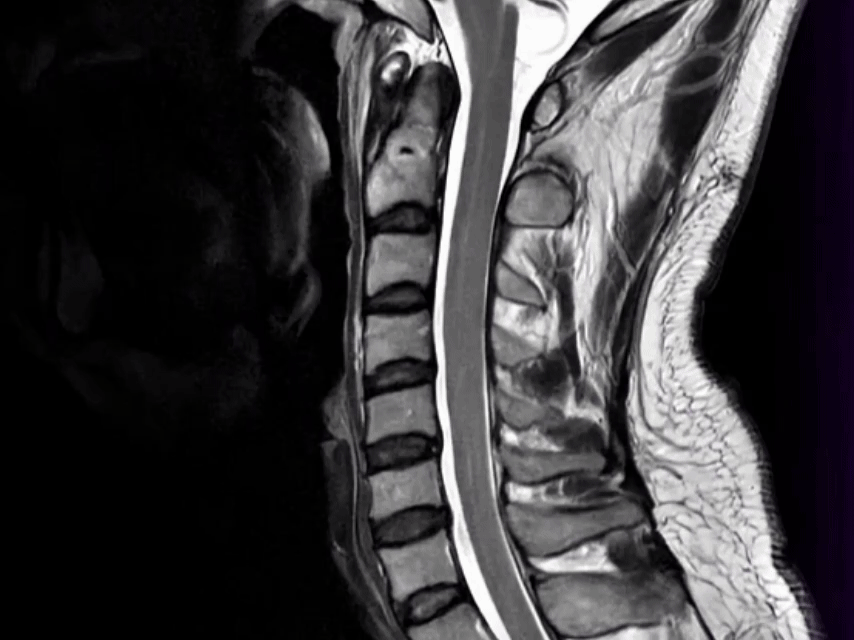

Kết hợp với MRI, chụp CT liều thấp giữ vai trò quan trọng trong tầm soát chuyên sâu, cho phép tái tạo hình ảnh cắt lớp của toàn bộ cơ thể (lồng ngực, bụng chậu, cột sống…) giúp nâng cao độ chính xác trong chẩn đoán.

• Chẩn đoán hình ảnh: CT scan toàn thân (cổ, ngực, bụng, chậu); MRI sọ não.